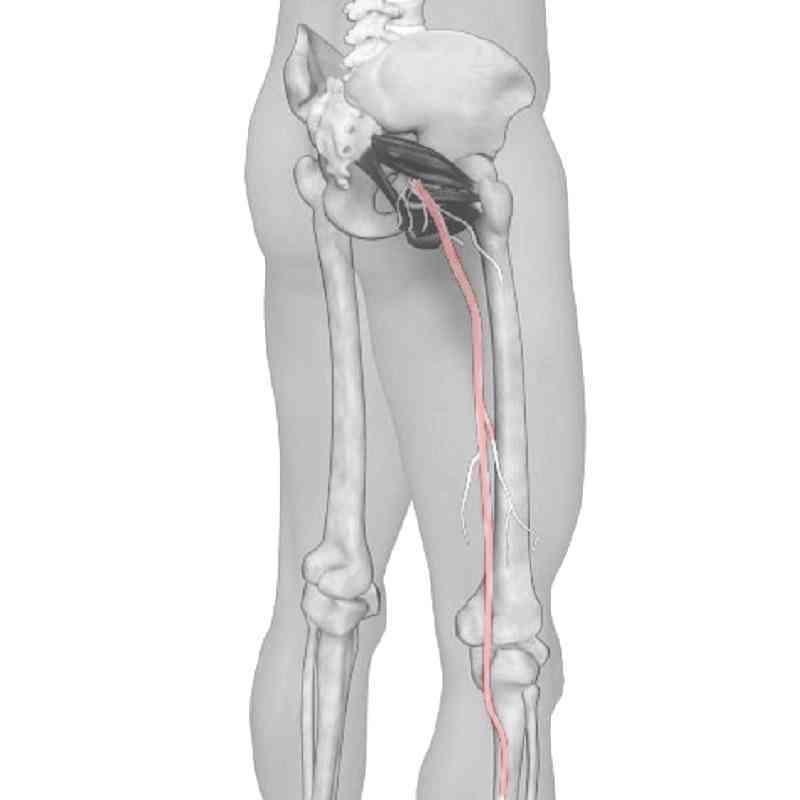

*若腰部傷患及炎症組織壓迫神經,則可出現腿部神經症狀,包括肌力減弱、麻痹和神經痛等。

腰椎間盤突出好發於中年壯年人士。椎間盤突出可壓迫神經線,症狀除腰背疼痛外,亦可產生沿坐骨神經線的神經痛。病人亦注意患病期的坐姿,避免坐梳化;注提舉重物的姿勢,嚴禁彎腰負重,並扭轉身體的動作;時刻保持腰部溫暖;盡早開始運動,可進行簡單鬆馳及強化腰部運動,例如平臥時曲膝擺腰動作,及平臥時曲膝提升臀部離床。